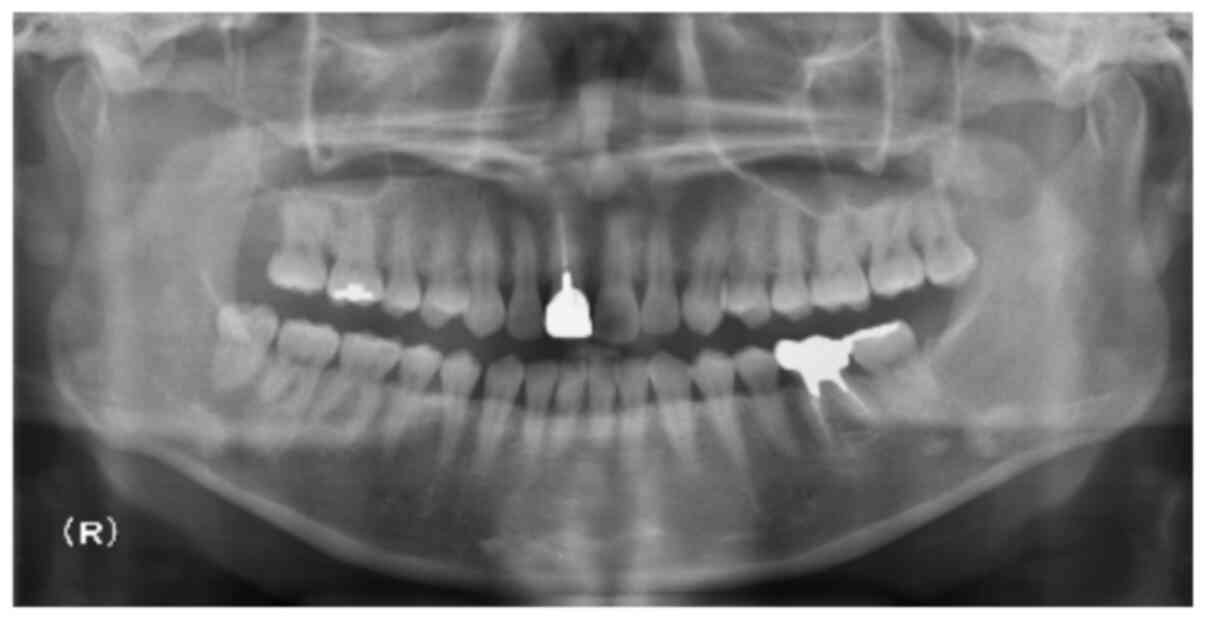

An otherwise healthy 39-year-old female patient was referred to our hospital having experienced right lower lip numbness for one month. She had no past medical history. Initial findings indicated no facial swelling or trismus. Intra-oral findings revealed no abnormal observation. Panoramic radiography showed that there were no bony lesions at the mandible. However, the right lower wisdom tooth showed signs of pericoronitis (Fig. 1). The patient received medication with antibiotics and Vitamin B12 to improve the pericoronitis and right lower lip numbness. Two weeks following referral, in spite of these medications, right lower lip numbness was not improved. Three months later, the right lower wisdom tooth was extracted, and subsequently right lower lip numbness was slightly improved.

Figure 1.

Panoramic radiograph. There were no bony lesions at the mandible.